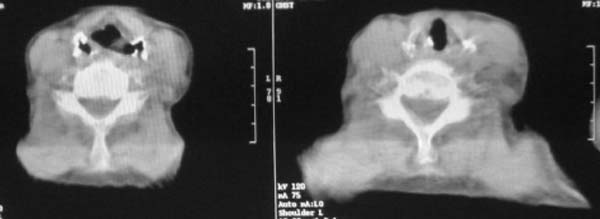

颈部见多枚淋巴结肿大,考虑尘肺继发结核,喉部淋巴结钙化,不除外喉部慢性淋巴结炎、喉淀粉样变及类癌等

颈部多个肿大淋巴结,考虑矽肺并结核

符合矽肺,另外甲状腺可见病变,需强化明确.

考虑尘肺继发结核,喉部淋巴结钙化,不除外喉部慢性淋巴结炎。

双上肺结节融合影,周围有纤维条索影,结合粉尘接触史,首先考虑尘肺。双侧颈部有增大淋巴结,有声嘶表现,肺癌淋巴结转移不能排除。可结合颈部淋巴结活检。